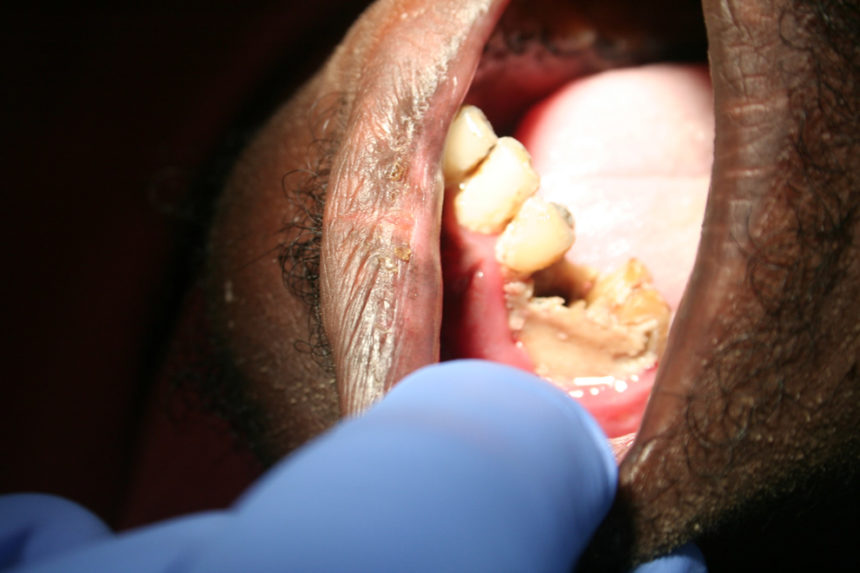

Kva er det så som møter ein tannlege som drar ut til ”the middle of nowhere”? Det er litt av kvart og det er svært sannsynleg at det vil dukke opp kasus som vi elles ser berre i lærebøker og patologiatlas.

Elles: To mandibelfrakturar, ein tumor som omfatta heile mellomansiktet på ei side og ei plommestor cyste i ganen.

Dei som kjem og søkjer hjelp har akutte problem. Det er smerter frå tenner med for store kariesangrep og det er små og store abscessar. Derfor er det ekstraksjon av molarar det dreier seg om! Retinerte visdomstenner er uvanleg.